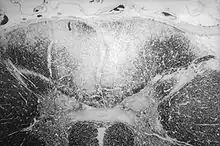

| Section of human skull damaged by late stages of neurosyphilis | |